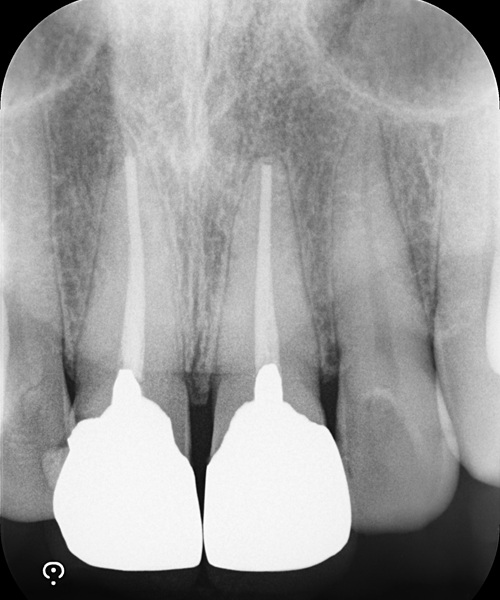

術前

| 治療名 | 精密根管治療と前歯セラミッククラウンによる審美修復症例 |

| 治療説明 |

以前に治療された前歯の被せ物の見た目を気にされ、再治療をご希望されました。 審美性だけでなく、内部の根管治療まで丁寧に行うことで、将来的なトラブルのリスクを抑えた、長期的に安定した治療結果を目指しました。 |

| 治療回数・期間 | 4回 |

| 副作用とリスク | ・保険診療の銀歯と比べて費用が高額になります。 ・根管治療からクラウン装着までを含めると、治療期間が長くなる傾向があります。 |

| 料金(税込) | 精密根管治療:88,000円×2本 セラミッククラウン:132,000円×2本 合計:440,000円(税込) |